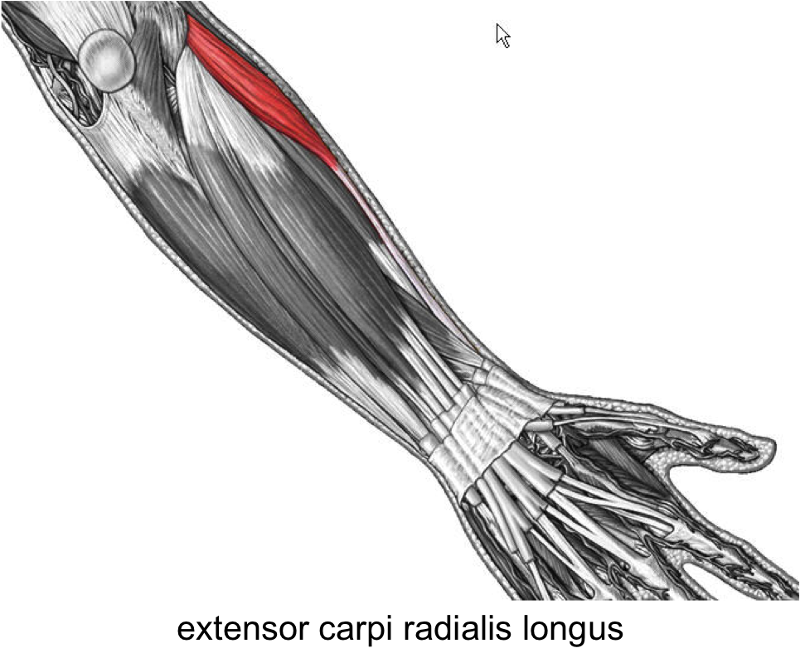

Анатомия и функции мышцы brachioradialis